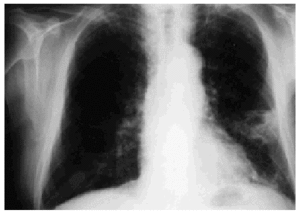

Noteworthy lab test results were as follows: an erythrocyte sedimentation rate of 48 mm/h, creatinine 3.70 mg/dL, urea 231 mg/dL, and serum gamma glutamyl-transferase 303 IU/L. A chest x-ray revealed irregular opacities in both apices and a cavitated infiltrate in the lower left lobe (Figure 1).

Fig. 1. Chest x-ray showing cavitated pulmonary infiltrate in the lower left lobe.